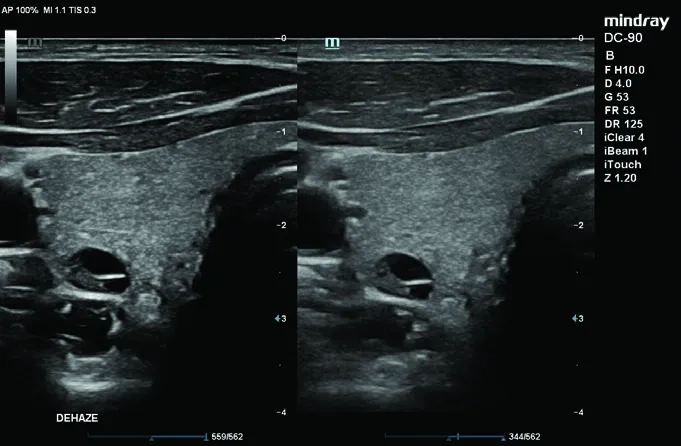

• iClear — адаптивное шумоподавление;

• iScape™ View — модуль панорамного сканирования.